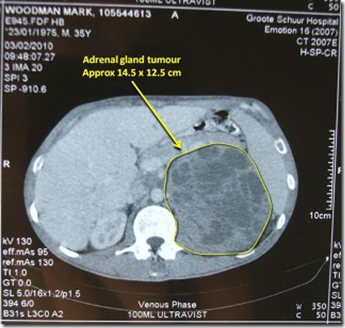

Adrenal Cortical Tumours Of Unusually Large Size

March 11, 1950 ADRENAL CORTICAL TUMOURS OF LARGE SIZE mediSH^rnal 583 In each case roughly spherical completely encapsulated tumours ... Read Full Source